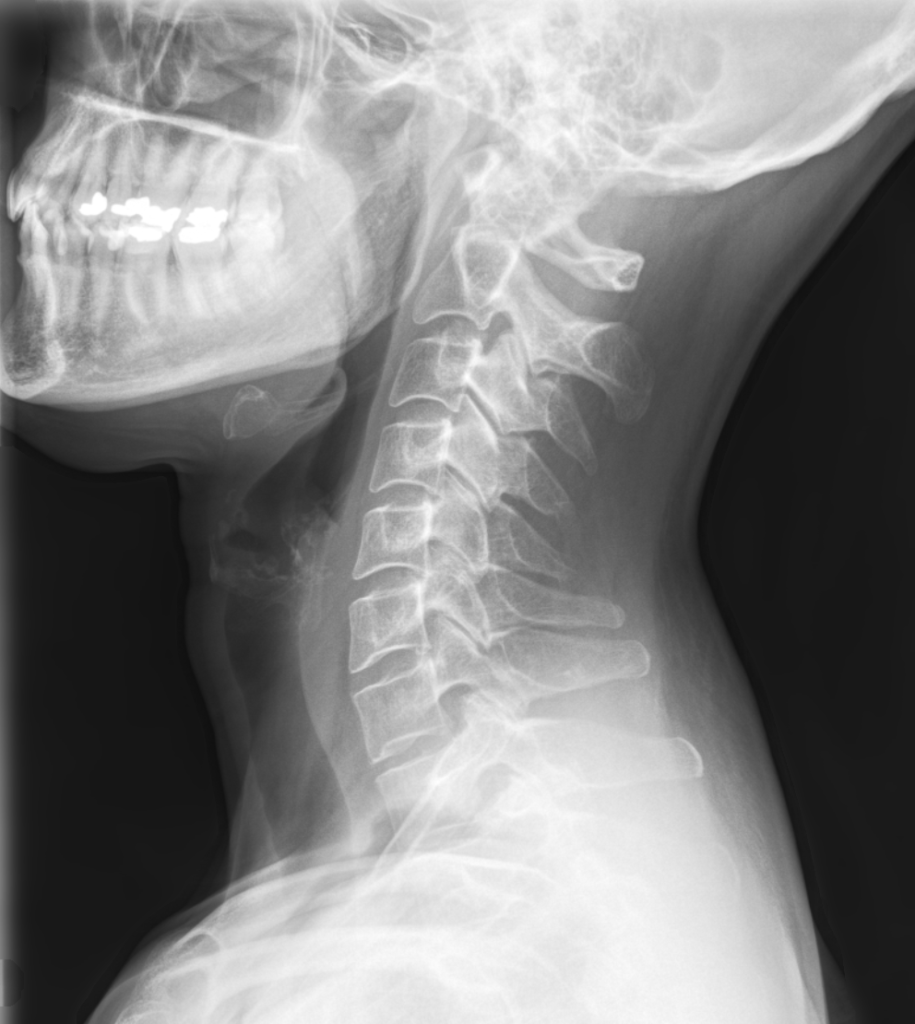

Is Chiropractic Neck Manipulation Safe . If you're in the habit of having your neck adjusted by a chiropractor, michigan medicine neurologist mollie mcdermott, m.d., wants to share some important. While chiropractic neck cracking is generally considered safe when performed by a trained and licensed professional, there are potential risks involved. These risks may include temporary discomfort, headaches, fatigue, or, in rare cases, more severe complications like arterial injuries. Low back pain, neck pain and headaches are the most common problems for which people seek chiropractic adjustment. Cervical spine manipulation (csm) is utilized by physical therapists, chiropractors, and other healthcare practitioners to treat a multitude of. Chiropractic neck manipulation, or cervical spinal manipulation therapy (csmt), is a common treatment approach used by chiropractors to. The association between chiropractic neck manipulation and stroke, though rare, underscores the importance of patient safety.